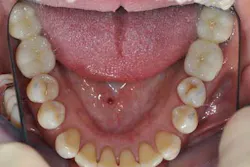

A 40-year-old woman, with no medical history except that she is a smoker (five cigarettes a day), is visiting us for an oral rehabilitation. Her chief complaints are teeth mobility and an esthetic concern since her maxillary front teeth are moving forward. The patient also suffers from dental anxiety.

Fig. 2: Anterior teeth relationships prior to treatment